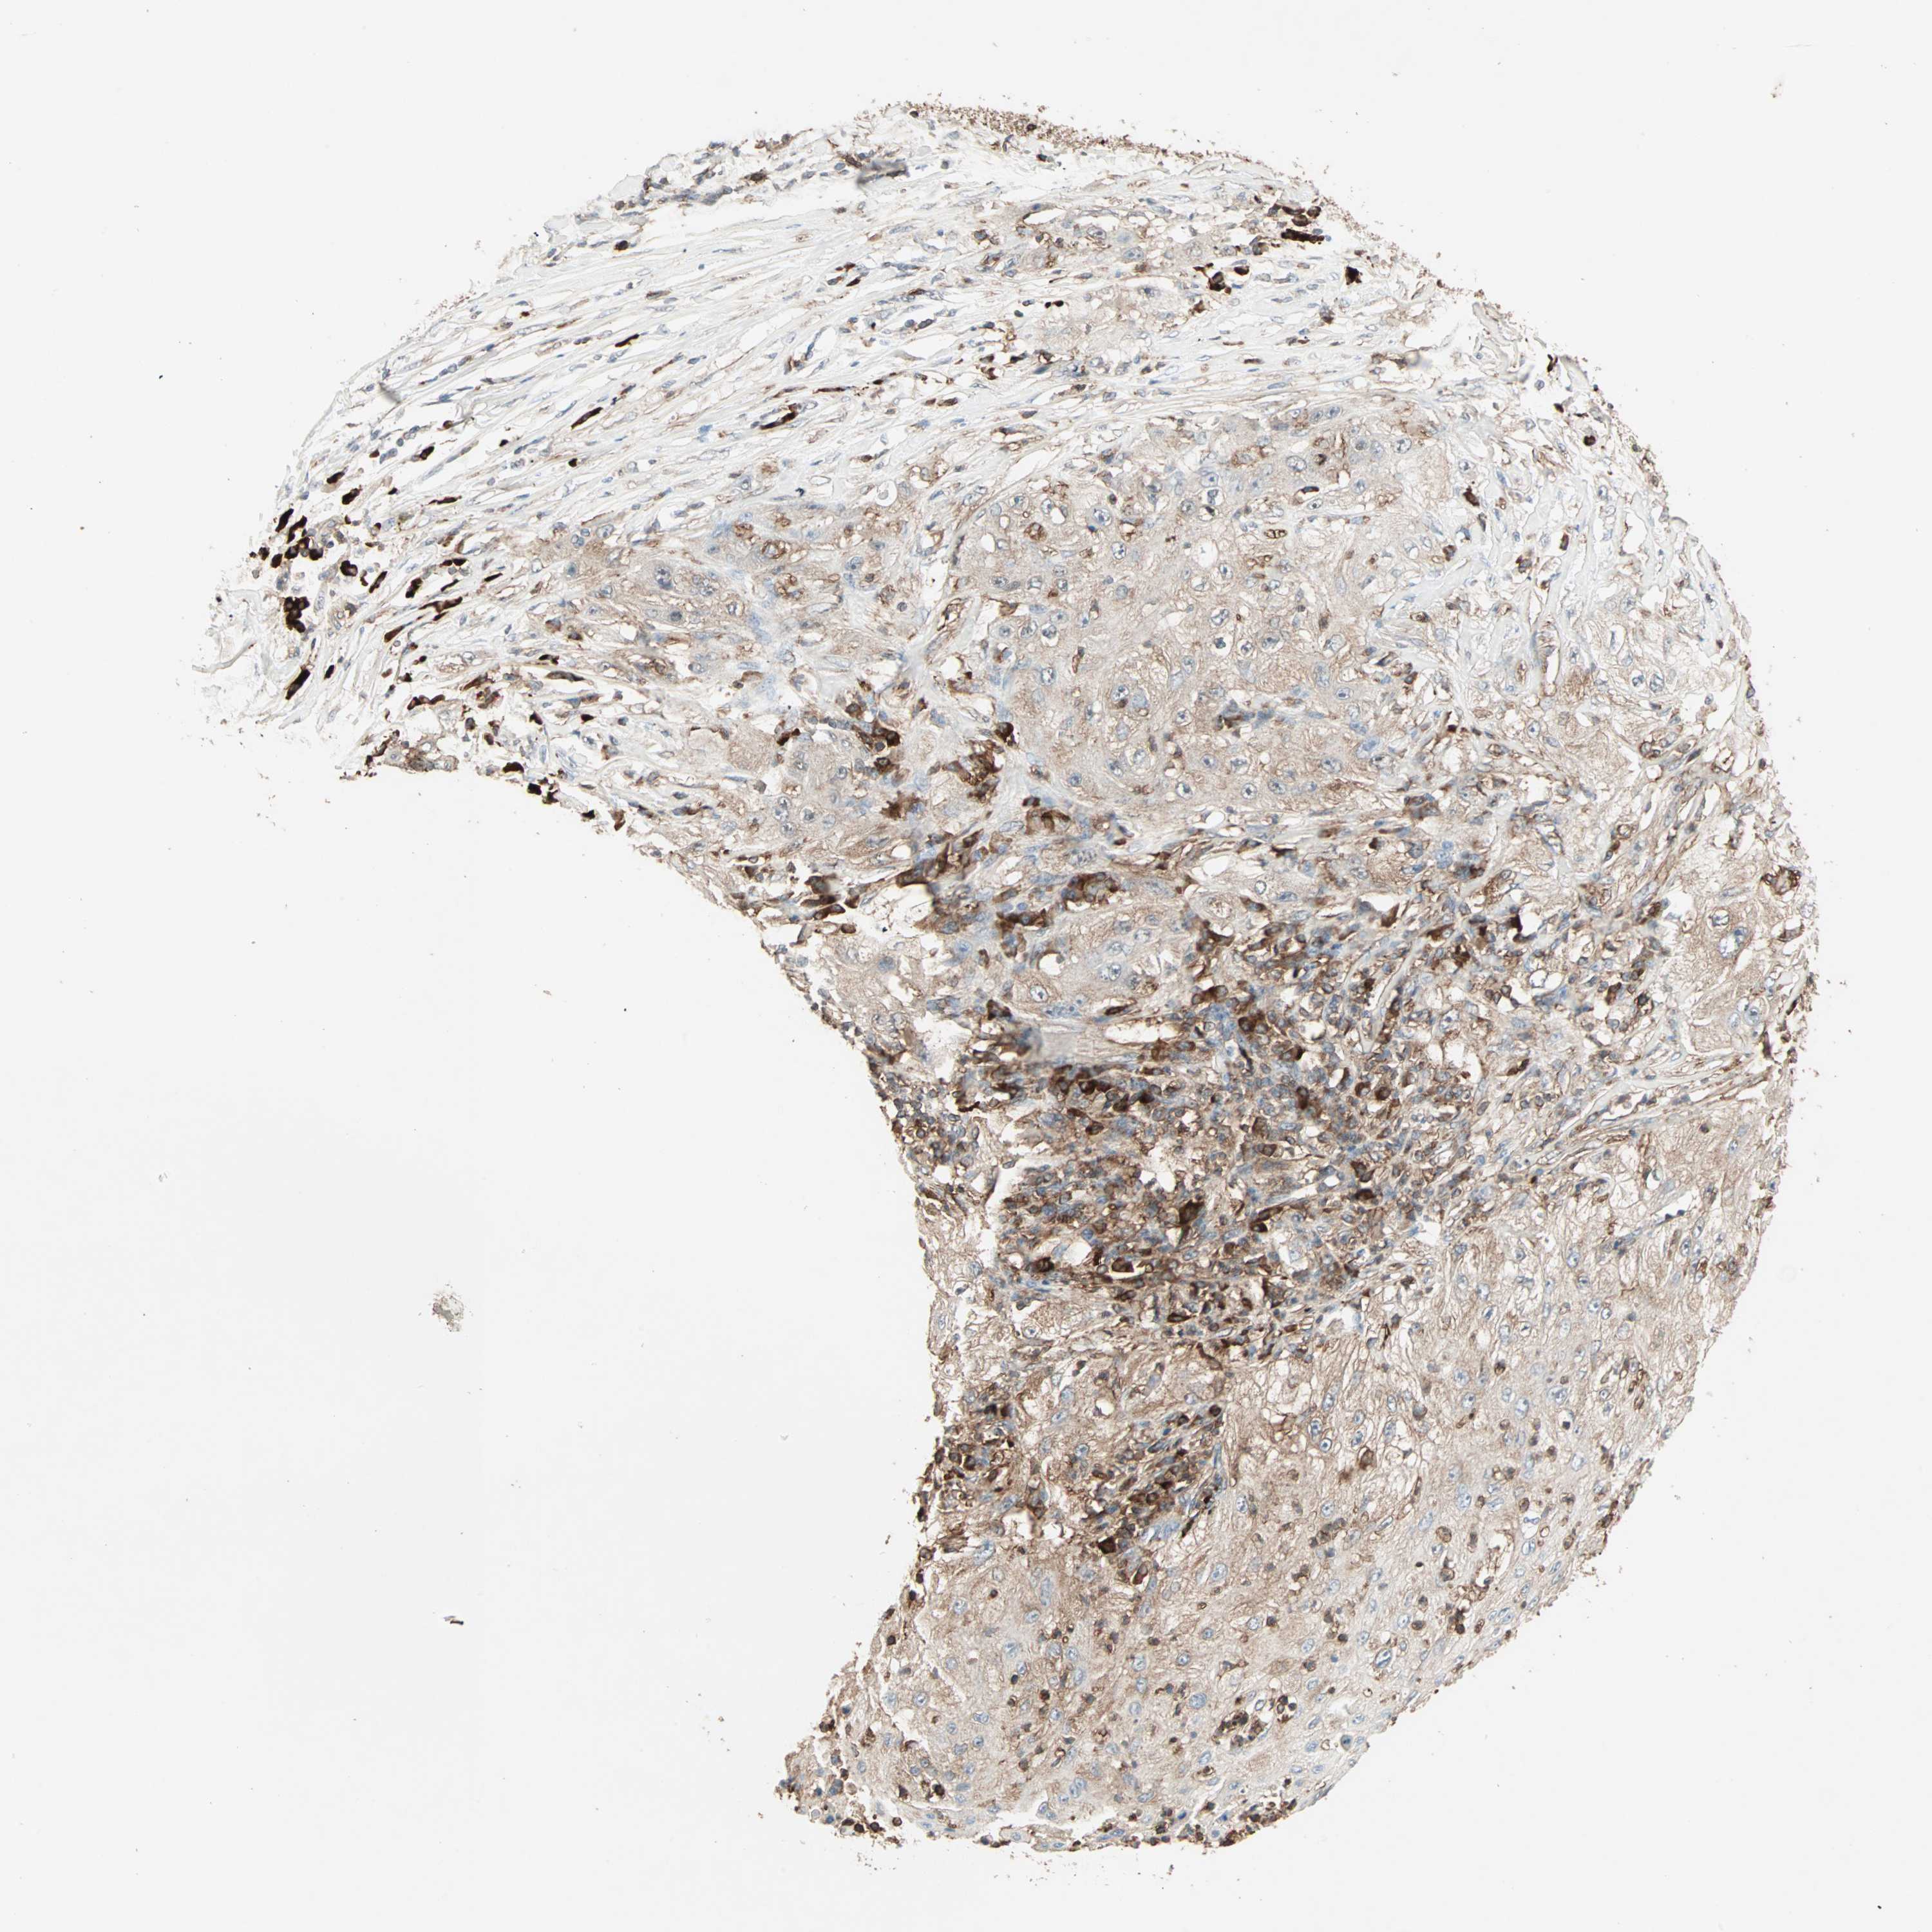

CANCER LUNG CANCER Show tissue menu

MMP3 is potential prognostic, high expression is unfavorable in Lung Adenocarcinoma (TCGA)